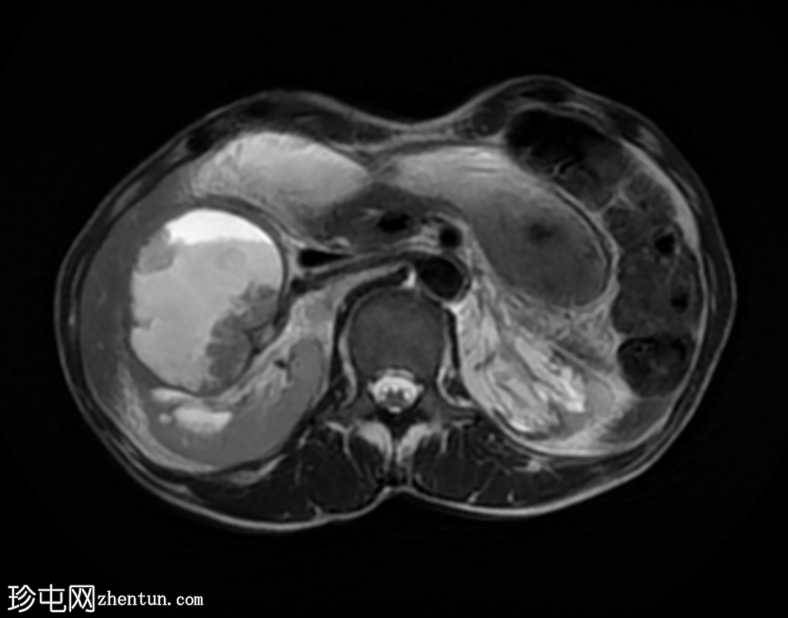

轴位

T2加权像

7.png

再次观察到上述肾前部外生性病变,其实性成分在T1加权像上呈等高信号,在T2加权像上呈低信号,伴有碎片扩散受限和低ADC值(化脓性物质)。囊性成分内部可见液-碎片/脓液界面。可见内部低信号结石。可见肾周模糊影。该病变压迫并可能侵犯右肾盂,导致中度肾积水。

病灶不规则的低信号,以及液-液界面伴有碎屑(可能为化脓性物质)扩散受限和肾周模糊,再次高度提示炎症性病变(黄色肉芽肿性肾盂肾炎,XGP),而非可能性较小的肿瘤。

左肾萎缩,体积较小,内含多发低信号结石。